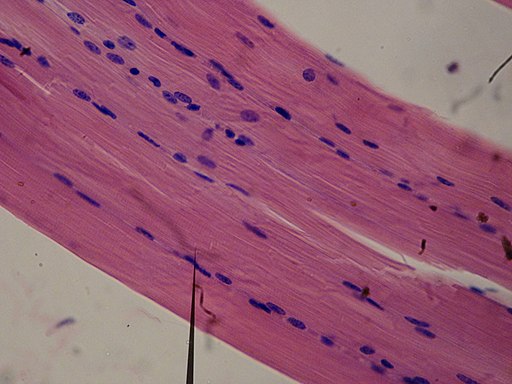

Anatomía microscópica

La anatomía microscópica también conocida como histología, es la disciplina que estudia los tejidos orgánicos, su estructura microscópica, su desarrollo y funciones. No solo estudia los tejidos, sino también de qué están compuestos.

Está rama de la anatomía es esencial para los estudios de medicina para entender los procesos patológicos que suceden en el cuerpo.